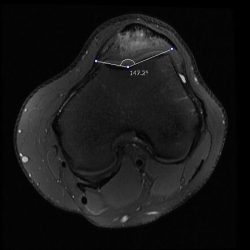

Figure1. Axial T2-weighted MR images show trochlear sulcus angle ...

Measurements for trochlear dysplasia: a sulcus angle (SA) is the angle ...